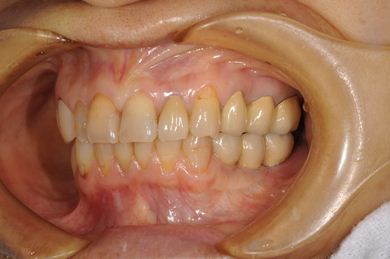

インプラントの症例写真 IMPLANT

骨再生インプラント治療+セラミック治療

| 治療内容 | インプラント6本(ソケットリフト)、ハイブリッドセラミック14本(ハイブリッドセラミック用土台5本、遊離歯肉移植術 | ||||||||||||||||||||||||||||||||

| 総治療費 | 2,751,445円 | ||||||||||||||||||||||||||||||||

| 治療期間 | 2年3ヶ月 |